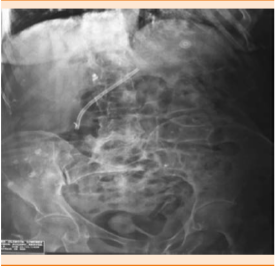

La paciente tuvo respuesta favorable a tratamiento con fluidoterapia, soporte respiratorio no invasivo, apoyo vasopresor, meropenem y vancomicina, con egreso hospitalario el 1 de noviembre de 2014. Fue llevada a Urgencias una semana posterior a su egreso por dolor abdominal y evacuaciones disminuidas en consistencia, en número de 10 ocasiones en 24 horas y temperatura axilar de 38.4ºC de 48 horas de evolución. Los estudios paraclínicos de ingreso evidenciaron: Hg 10.5 g/dL, HCTO 32.5%, VCM 88 fl, HCM 28 pg, plaquetas 558,000 μL, leucocitos 14,600 μL, neutrófilos 83%, bandas 3%, linfocitos 5%. Ingresó al servicio de Medicina Interna con reporte de toxinas A/B de Clostridium difficile en heces positivas, por lo que se diagnosticó colitis pseudomembranosa secundaria a antibióticos y se inició tratamiento con metronidazol IV/VO, con adecuada respuesta clínica, por lo que egresó el 10 de noviembre de 2014. Acudió a Urgencias el 24 de noviembre de 2014 por adinamia, hiporexia, alza térmica y calosfríos, a la exploración física tenía candidiasis esofágica (Candida score de 91 puntos con riesgo intermedio de candidiasis invasiva), el ultrasonido abdominal reportó datos compatibles con coledocolitiasis e hidrocolecisto y recibió tratamiento con colangiopancreatografía retrógrada endoscópica + colecistectomía laparoscópica; además, recibió tratamiento antibiótico con ceftriaxona y fluconazol IV. La paciente egresó por mejoría el 30 de noviembre de 2014 con estudios paraclínicos de control de Hg 14 g/dL, HCTO 44%, VCM 88 ft, HCM 26 pg, plaquetas 238,000 μL, leucocitos 17,500 μL, neutrófilos 71%, bandas 18%, linfocitos 3%. Reingresó a cargo del servicio de Cirugía general el 31 de diciembre de 2014 con diagnóstico de colangitis. En la colangiopancreatografía retrógrada endoscópica se encontró estenosis de la vía biliar extrahepática y se colocó cánula de derivación, se prescribió tratamiento antibiótico con metronidazol y ciprofloxacino (Figura 2).